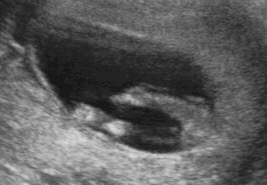

Attachment 31549

Maybe boy based on second pic

The first pic looks girly to me but then the second pic looks boyish. Sorry, I know that doesn't help!

Maybe boy based on second pic, but not the best pics, so could well be a girl too.

What do ya'll see in the second pic?? I am having a hard time seeing the nub end due to the fuzziness.